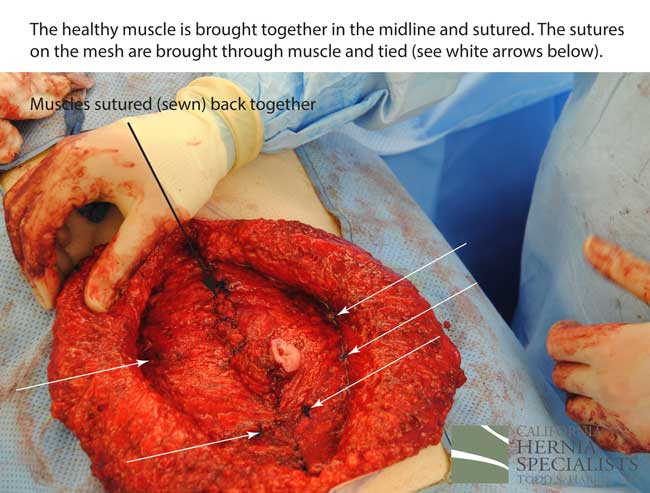

The more complete approach would be to bring healthy muscle together at the mid line. Only after the muscle is repaired completely, can a mesh be used to SUPPORT the muscle repair. Meshes should not be considered a bridge from healthy muscle to healthy muscle. Instead mesh should be used as a reinforcement of a correct hernia repair.

This technique requires more surgical time, recovery time, and usually several days in the hospital. However, this patient chose to proceed with the open hernia repair. Below are some of the pictures from his surgery as well as post operative CT scan image and photos of the patient.

Because this patient had failed two prior surgeries, we performed a complex open hernia repair on him. This repair included a technique called ‘component separation’, where the oblique muscles on the sides of the abdomen, are partially released, or cut, to allow the rectus muscles to be pulled back together in the middle of the abdomen.

Since the abdominal muscles were weakened, we placed a sheet of biologic mesh under the muscle in the middle at the area of the hernia hole, closed the muscle over this mesh, then placed another mesh on top of the muscles which were closed. This provided him with three layers of repair.